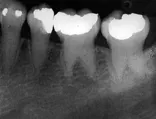

The problem: Radiographic examination revealed teeth with short W-shaped roots and obliterated pulp chambers

The problem: Radiographic examination of the area revealed a well-defined cyst with corticated borders distal to the roots of tooth #31.

The problem: Radiographic examination revealed mixed lucent-opaque lesions around the apices of teeth #24 and #25.